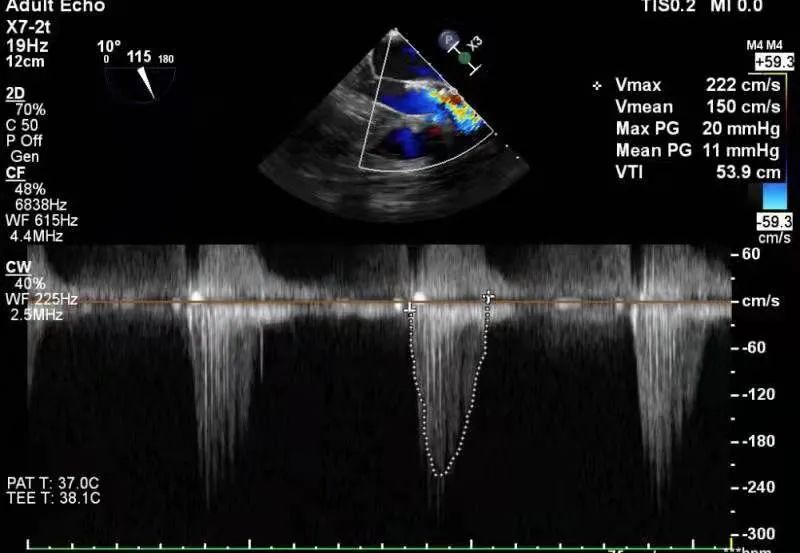

术前、术后患者跨瓣压差对比

考虑患者窦部结构较小,为避免发生冠脉风险,选择不予以后扩。超声提示患者跨瓣压差即刻显著下降,反流量较术前明显改善。术中未出现相关并发症,术后患者心功能持续得到改善,效果良好,圆满取得此次手术成功。